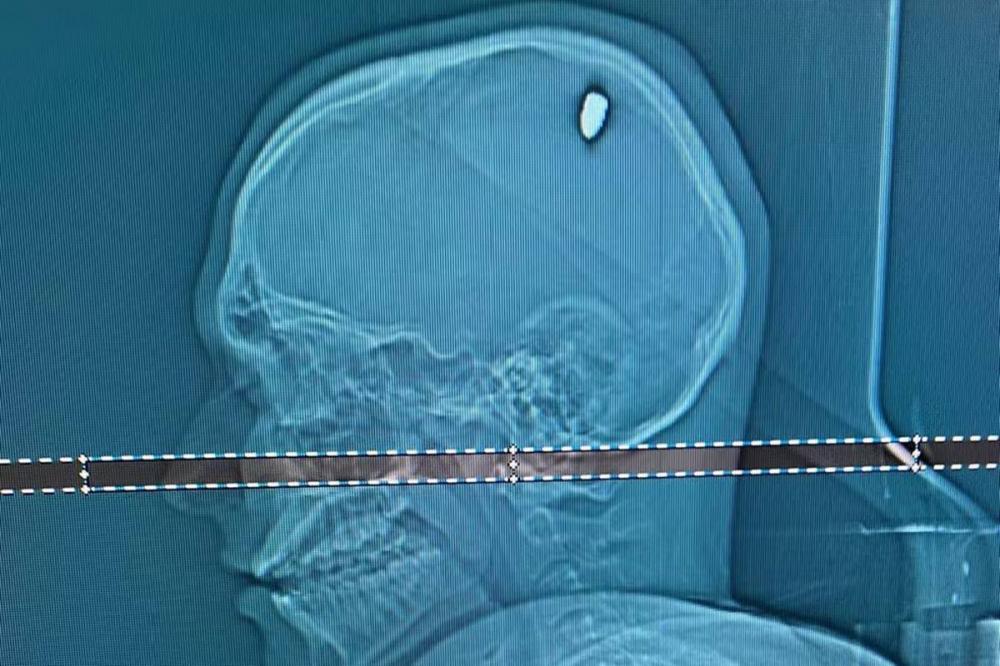

Jovem é atingido por bala perdida na cabeça e só percebe 4 dias depois

Mateus Facio, 21 anos, sentiu uma forte dor na cabeça na virada do ano, mas pensou ter sido atingido por uma pedra